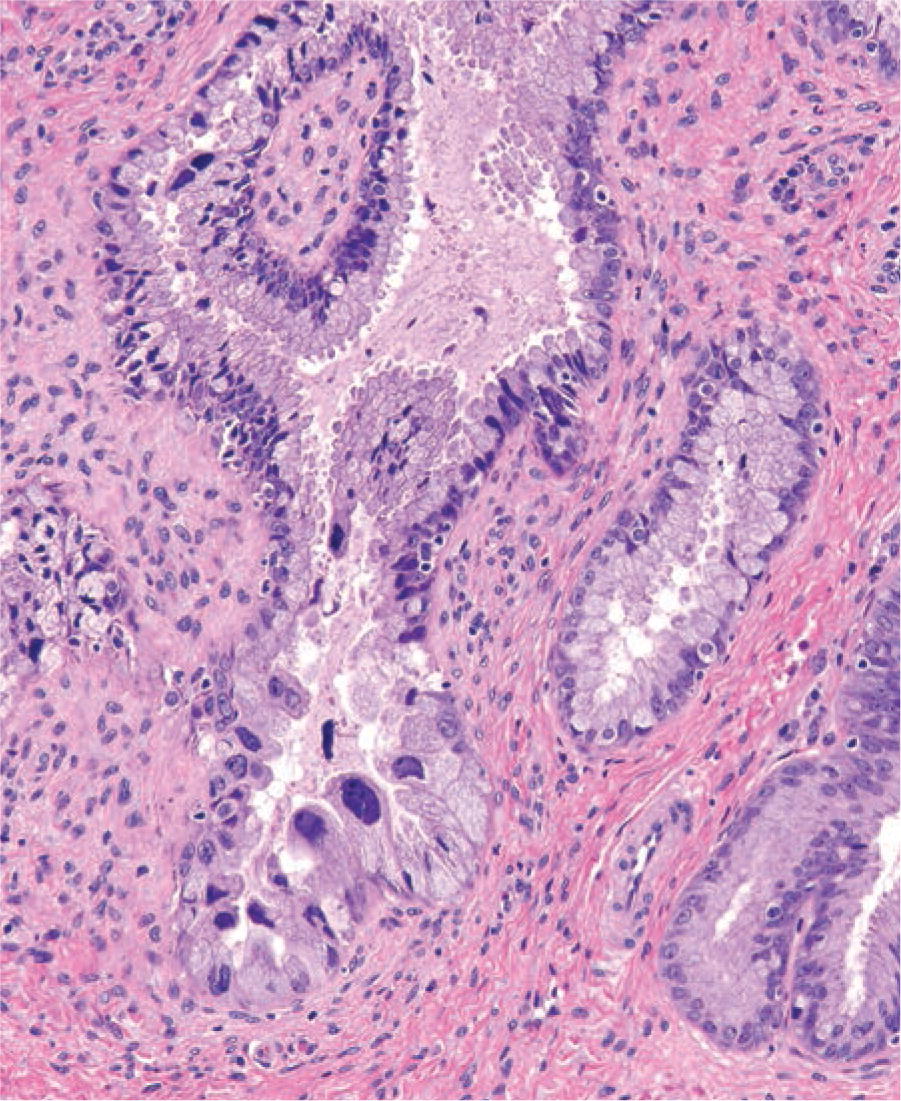

Benign atypical endometrial changes associated with chorionic tissue. [1] may be seen in a. The epithelial cells lining the glands undergo a characteristic morphological change during early pregnancy, referred to as the arias.

Arias Stella Reaksiyonu Ne Demek The epithelial cells lining the glands undergo a characteristic morphological change during early pregnancy, referred to as the arias. Benign atypical endometrial changes associated with chorionic tissue. The epithelial cells lining the glands undergo a characteristic morphological change during early pregnancy, referred to as the arias. [1] may be seen in a.